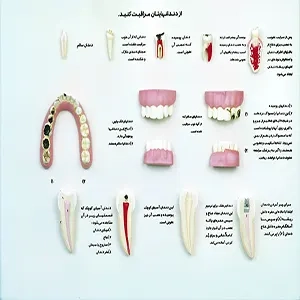

- مولاژهای دندانی: برای آموزش و تمرین در زمینه دندانپزشکی، شامل مدلهایی از دندانها و ساختارهای دهان.

- مولاژهای دندانپزشکی: شامل مدلهای دندان، لثه و ساختارهای مربوطه برای آموزش و تمرین در دندانپزشکی.

مولاژهای دندانپزشکی: برای آموزش و تمرین تکنیکهای دندانپزشکی، شامل:

- ماکتهای دندان و لثه: برای آموزش ساختار و درمانهای دندانپزشکی.

- ماکتهای جراحی دندان: برای تمرین تکنیکهای جراحی دندانپزشکی.

2. مولاژهای دندانپزشکی

- ماکتهای دندان و لثه: برای آموزش درمانهای دندانپزشکی و آناتومی دندان. برندهایی مانند Coltene و Dental Models انتخابهای خوبی هستند.

- ماکتهای جراحی دندان: برای تمرین جراحیهای دندانپزشکی. برندهای معتبر شامل KaVo و A-Dec هستند.

مولاژهای دندانپزشکی: برای آموزش و تمرین در دندانپزشکی، مولاژهایی مانند مدلهای دندان و فک وجود دارند. قیمت این مولاژها معمولاً بین ۵۰ تا ۵۰۰ دلار است.

۲. مولاژهای دندانپزشکی

این مولاژها برای تمرین و آموزش تکنیکهای دندانپزشکی استفاده میشوند:

- مولاژهای دندان: شامل دندانهای طبیعی یا مصنوعی برای آموزش نحوه درمان و ترمیم دندانها.

- مولاژهای فک و لثه: برای مطالعه ساختار فک و لثه و تمرین تکنیکهای جراحی و درمان.